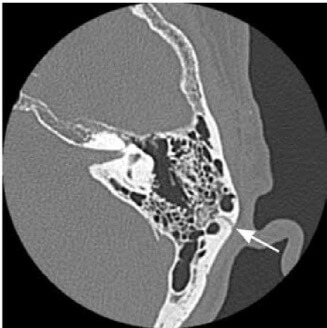

★ 側頭骨のターゲットCT

耳を中心に、耳小骨の細かい変化を撮影する方法です。耳の構造は、骨によって作られているので、骨の変化を見ることにより、種々の外傷性変化を確認することができ、撮影時間が短く、小さな子どもでも耐えられる検査です。

★ 側頭骨ターゲットCTの利点

1. ターゲットCTは、他の検査に比べて、解像度が良く、骨の描出に優れている

2. 1mm以下のスライス厚で再構成が可能で、より細かいものまで見ることができる

3. 撮影時間が5分と短く、患者さんの負担が軽い

4. 横断像だけなく、CTの3次元データから冠状断を作成することが可能である